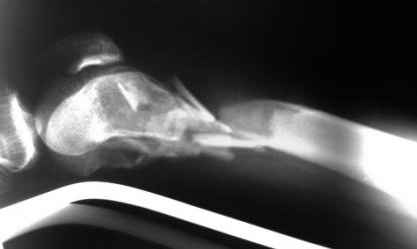

Рентгенограммы.

На рентгенограммах перелом не "н/3" бедра, что подразумевает диафиз, а перелом дистального суставного конца - крупные фрагменты мыщелков, метафиз фрагментирован, т.е. по классификации OTA/AO это 33C2.

Право слово, классификация переломов существует не зря, она помогает и выбрать вариант остеосинтеза, и даже в отсутствие рентгенограмм можно более точно обозначить проблему.

Наиболее широко распространенный подход в такой ситуации - после репозиции мыщелков использовать пластину с угловой стабильностью.

Можно и ретроградное штифтование, если есть соответствующий гвоздь.

При любом варианте фиксации надо избежать соблазна залезать открыто в метадиафизарную часть повреждения.

Мы бы начали с закрытой репозициии мыщелков под экраном, манипулируя джойстиками. Если не получается - миниартротомия. Сопоставленные мыщелки прошили бы спицами (резервируя место для гвоздя). Наложили бы спицевой дистрактор. И сделали бы антеградное штифтование гвоздем с

несколькими очень дистально расположенными отверстиями.